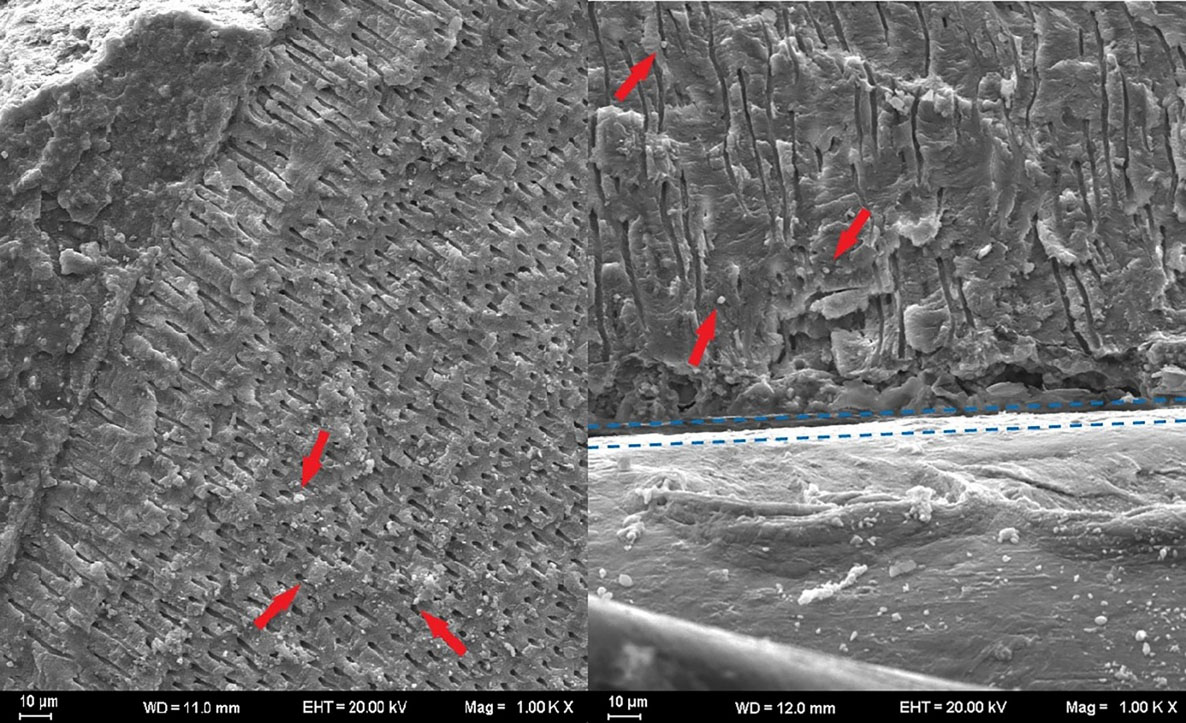

Samples were examined with a scanning electron microscope to visualize the depth of penetration of the root canal sealer. One sample from each group was selected and prepared for SEM examination. The specimens were marked using a diamond disk and divided longitudinally into two sections; both sections were used for SEM analysis. The prepared samples were sputter-coated and placed into the vacuum chamber of the scanning electron microscope (Carl Zeiss NTS GmbH, Oberkochen, Germany). Sealer penetration and adaptation were examined from the coronal to apical ends at ×1000 magnification, and microphotographs were taken ().

Figure 3.

SEM images of the dentin surface (red arrows: root canal sealer particles; blue dashed lines: border between the root canal filling and the dentin).